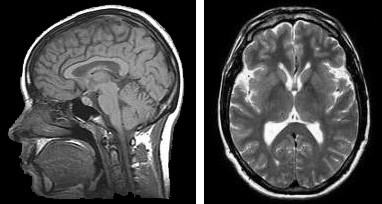

Magnetic resonance imaging.

This poem was inspired by a question on twitter, asking if a MRI could inspire poetry?